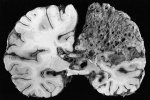

Прионные заболевания — это редкие, но смертельно опасные болезни, которые вызывают необратимое поражение головного мозга. Их основная опасность заключается в 100% летальности, отсутствии лечения и уникальной природе возбудителя — не вируса или бактерии, а обычного белка с аномальной структурой .

Симптомы разнообразны и зависят от типа заболевания, но всегда связаны с поражением нервной системы. Ниже подробно разобраны ключевые аспекты.

Почему прионы так опасны?

· Необычный "возбудитель": Прион — это не микроб, а измененный (неправильно свернутый) белок, который вызывает цепную реакцию, превращая нормальные белки мозга в себе подобные .

· Неуязвимость: Прионы не разрушаются при кипячении, обработке формалином или радиацией. Стандартные методы стерилизации хирургических инструментов против них бессильны .

· Неизлечимость: Современная медицина не может остановить развитие болезни. Врачи способны лишь временно облегчать симптомы пациента .

· Скрытое течение: Инкубационный период может длиться годами и даже десятилетиями, но после появления первых признаков болезнь быстро прогрессирует .

Основные симптомы (клиническая картина)

Симптомы зависят от того, какой участок мозга поражается сильнее. Для удобства их можно разделить на группы:

Группа симптомов Как проявляется Примеры заболеваний

Психические и когнитивные нарушения Это часто самые ранние признаки. Наблюдаются быстрая потеря памяти, деменция, изменения личности (раздражительность, апатия), депрессия, тревожность, бессонница . Спорадическая болезнь Крейтцфельда-Якоба (БКЯ), Фатальная семейная бессонница .

Двигательные расстройства Нарушение координации (атаксия) — шаткая походка, дрожание рук (тремор), мышечная скованность (ригидность), резкие непроизвольные вздрагивания (миоклонии). На поздних стадиях возможны параличи . Болезнь Крейтцфельда-Якоба (БКЯ), Синдром Герстманна-Штраусслера-Шейнкера .

Другие неврологические знаки Нарушения зрения (вплоть до слепоты), затруднения речи (дизартрия), проблемы с глотанием (дисфагия), эпилептические припадки . Куру ("смеющаяся смерть" — сопровождается приступами беспричинного смеха), Вариант болезни Крейтцфельда-Якоба .

Симптомы со стороны внутренних органов Встречаются при редкой наследственной форме. Характерны длительная диарея, вздутие живота, потеря веса, недержание мочи, головокружение при вставании . Прионная болезнь, связанная с диареей и вегетативной нейропатией .

Как можно заразиться?

Заболевание может возникнуть тремя путями :

1. Спорадически (85-90% случаев) : Болезнь возникает случайно, без видимой причины, чаще у людей старше 50-60 лет.

2. Наследственно (10-15%) : Мутация в гене передается по наследству. К этой группе относятся фатальная семейная бессонница и синдром Герстманна-Штраусслера-Шейнкера.

3. Приобретенно (крайне редко) : Заражение происходит извне — например, при употреблении в пищу мяса больных коров (вариант болезни Крейтцфельда-Якоба, "коровье бешенство"), при пересадке зараженных тканей или использовании загрязненных нейрохирургических инструментов .

Резюме: Прионные болезни — это всегда смертельный диагноз. Любые сочетания быстро прогрессирующей деменции с двигательными нарушениями (особенно миоклонией) и психическими расстройствами — повод для срочного обращения к неврологу, хотя, к сожалению, изменить исход заболевания современная медицина пока не в силах.